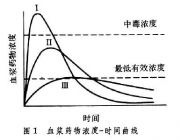

| 2021年7月26日 (一) 20:03 | 血浆药物浓度-时间曲线.jpg (文件) |  |

26 KB | Uploaded with SimpleBatchUpload | 3 |